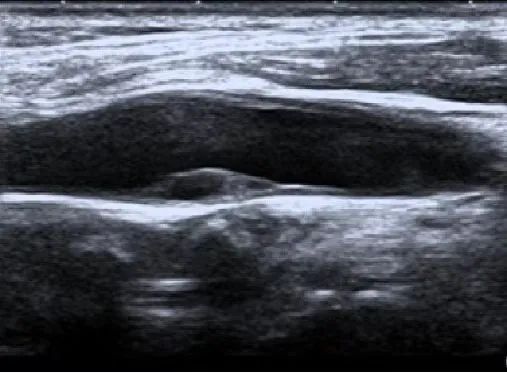

颈动脉斑块 超声示意图

颈动脉超声是诊断和评价颈动脉壁疾病的有效方法之一。检查的目的是判断有无血管壁增厚,硬化或狭窄等。正常颈动脉血管内中膜无增厚、无斑块形成,血管不狭窄,无闭塞。

颈动脉彩超不仅能清晰显示血管内中膜增厚、有无斑块形成、斑块形成的部位、大小、是否有血管狭窄及狭窄程度、有无闭塞等详细情况,并能进行准确的测量及定位,还能对检测动脉血流速度及阻力进行测量。特别是可检测早期颈动脉粥样硬化病变的存在,使患者得到及时预防。